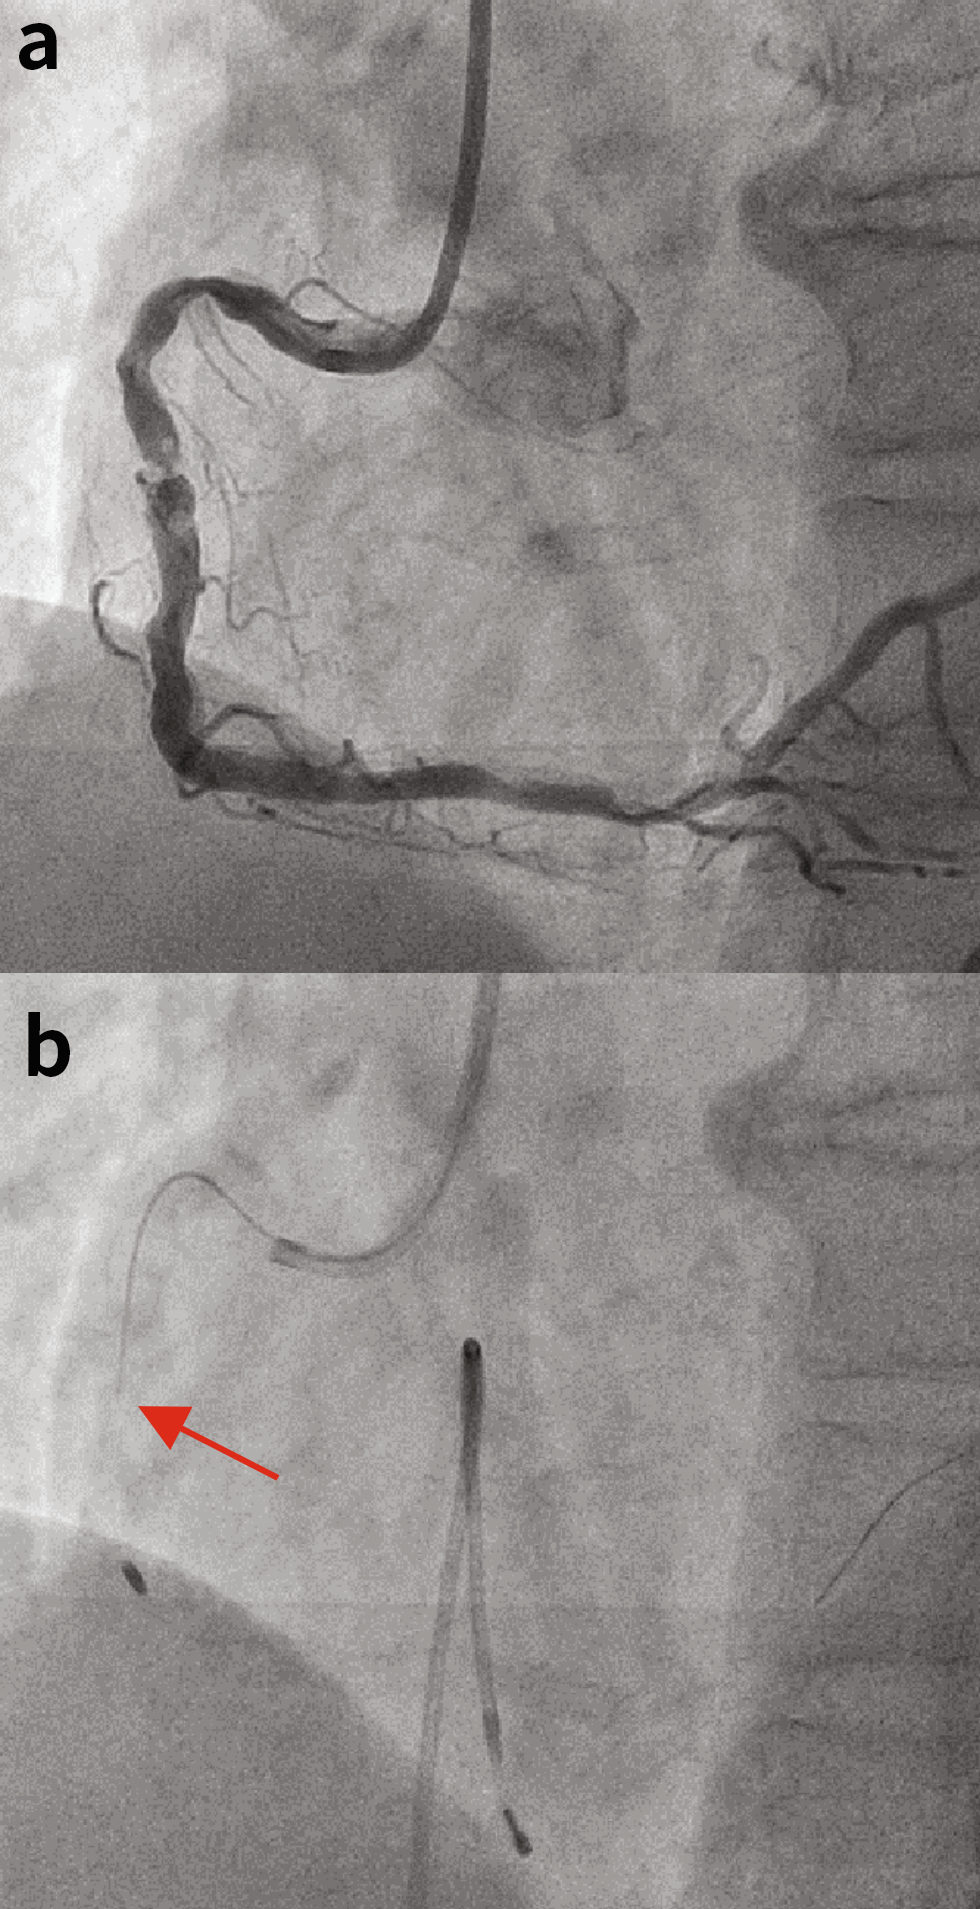

患者男性,67岁,长期接受血液透析,冠脉造影显示右冠状动脉(RCA)近端存在弯曲的中度钙化狭窄病变,RCA中段存在重度狭窄病变并伴有严重钙化(图1(a))。通过股动脉送入7-Fr JR4.0指引导管,并将SION blue导丝送至RCA远端。

由于IVUS和小直径球囊无法通过(视频1),因此使用微导管将SION blue导丝替换为旋磨导丝。以180,000转/分的转速并采用缓慢的前后“啄米式”运动(每次运行最多20秒),通过消蚀RCA近端部分,将1.5mm磨头推进。将转速保持在175,000转/分以上。随后,对中段重度狭窄病变进行消蚀。然而,我们观察到,尽管驱动轴被来回拉动,但当旋磨头推进到远端RCA时,旋磨头从驱动轴上脱落(图1(b)和图2(b),视频2和视频3)。幸运的是,冠脉前向血流得以保持,且旋磨导丝没有断裂。

图1.(a)基线冠状动脉造影。(b)驱动轴与磨头分离(红色箭头表示驱动轴的边缘)。

图2. (a)最终冠状动脉造影。(b)断开的旋磨头和驱动轴的边缘(红色箭头)。(c)旋磨导丝的远端和主体部分。